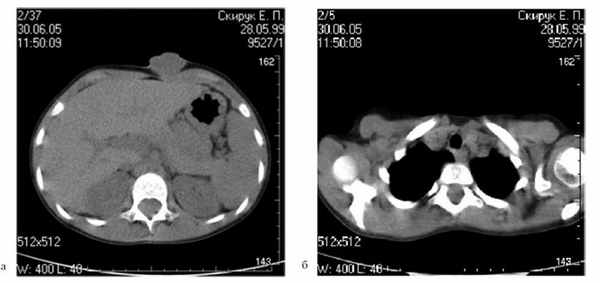

У 4 детей при метастазах в регионарных лимфатических узлах или при подозрении на таковые одновременно с широким иссечением произведена лимфодиссекция. У 3 из них выявлены множественные метастазы в лимфатических узлах. Им дополнительно проводили химиотерапию и/или биотерапию и лучевую терапию. Одному из этих детей (11 лет) проводили химиотерапию дакарбазином в комбинации с тамоксифеном. Всего проведено 4 курса химиотерапии с интервалом 3—4 нед. После завершения химиотерапии провели биотерапию Интроном А (ИФН-α2b) до 6 мес. Второму пациенту (12 лет) провели биотерапию Интроном А согласно рекомендациям EPOG-1684 и лучевую терапию в суммарной дозе 36 Гр на пораженную зону лимфатического аппарата [20]. У третьего ребенка (6 лет) имелась невероятно большая пигментная меланома кожи передней брюшной стенки (толщина опухоли 22 мм) с множественными метастазами в лимфатических узлах обеих подмышечных областей (рис. 1). Рисунок 1. Компьютерная томограмма органов грудной клетки и живота больной 6 лет с пигментной меланомой кожи передней брюшной стенки с метастазами в лимфатических узлах обеих подмышечных областей: а — меланома кожи передней брюшной стенки толщиной 22 мм с переходом на апоневроз; б — массивное метастатическое поражение подмышечных лимфатических узлов с обеих сторон. Больной провели 4 сеанса общей гипертермии с введением дакарбазина в курсовой дозе (системная термохимиотерапия) [22].